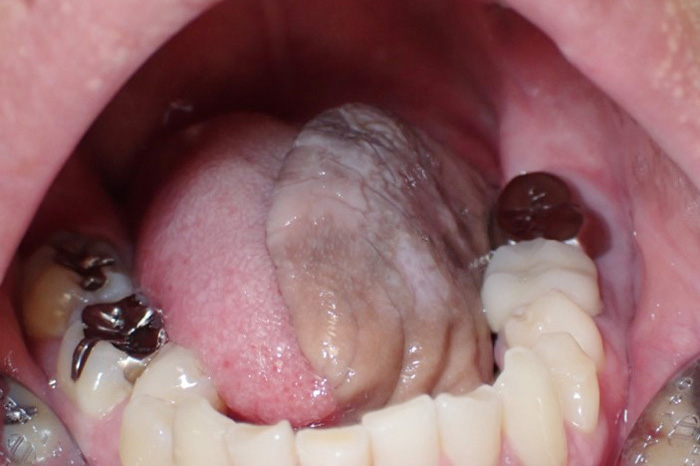

令和4年から口腔腫瘍科を新たに開設させていただきました。口腔腫瘍科で主に扱う疾患は口腔がん(舌がん、歯肉がん、頬粘膜がん、口蓋がん、口底がんなど)です。また、口腔潜在的悪性疾患としての前がん病変(白板症、紅板症など)や、前がん状態(口腔扁平苔癬)なども取り扱います。治療については手術療法、化学療法、放射線療法などを疾患により組み合わせて行います。広範囲にわたる手術などは関係各科と連携・協力し適切に進めていきます。

代表画像(舌がん)

舌がん

治療後(前腕皮弁で再建)